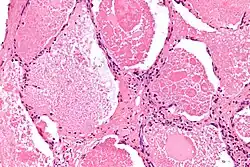

Micrograph of pulmonary alveolar proteinosis, showing the characteristic airspace filling with focally dense globs referred to as chatter or dense bodies. H&E stain.

Lung washings or tissue for histopathologic analysis are most commonly obtained using bronchoalveolar lavage and/or lung biopsy.[13] Characteristic biopsy findings show filling of the alveoli (and sometimes terminal bronchioles) with an amorphous eosinophilic material, which stains strongly positive on PAS stain and the PAS diastase stain. The surrounding alveoli and pulmonary interstitium remain relatively normal.[14] Electron microscopy of the sample, although not typically performed due to impracticality, shows lamellated bodies representing surfactant.[15] An alternative diagnosis with similar histomorphologic findings is Pneumocystis jirovecii pneumonia.[15]

Lung washings characteristically yield a fluid which is "milky"composition. Under the microscope, samples show 20-50 micrometer PAS-positive globules on a background of finely granular or amorphous PAS-positive material. There is typically a low numbers of macrophages and inflammatory cells (although this is variable).[14][15]